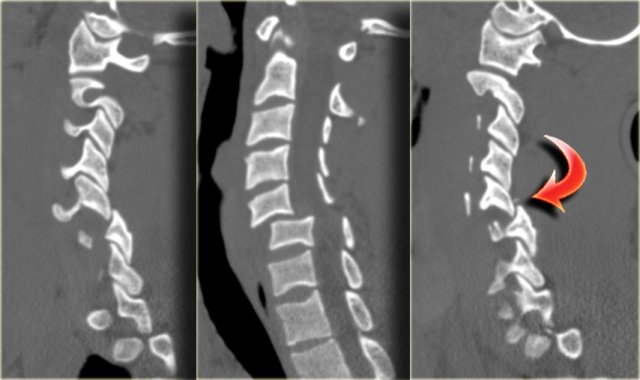

On the left images of a 44 year old female, who sustained a fall on the ice.

She subsequently had a second fall the following morning, where after she had complete loss of motor and sensation.

On physical examination there was lower extremity paraparesis with some upper extremity weakness on the right.

Central cord injury was proposed initially.

The radiographs were normal.

The findings are:

- Small bone fragmets comming off the superior and inferior facets

- Widened interspinous space at C5-6

- Soft tissue swelling at this level posteriorly

- Subtle narrowing of the disc space at the C5-6-level.

These CT-findings are very subtle and do not seem to match the neurological problem.

In such a case MRI is the next step.

First we show you a coronal and axial CT with also a soft tissue window-setting.

There is high density material at the back of the disc space, which is very suggestive for a traumatic disc herniation.

A epidural hematoma should be in the differential, but this finding was limited to just the area of the disc space, unlike a hematoma.